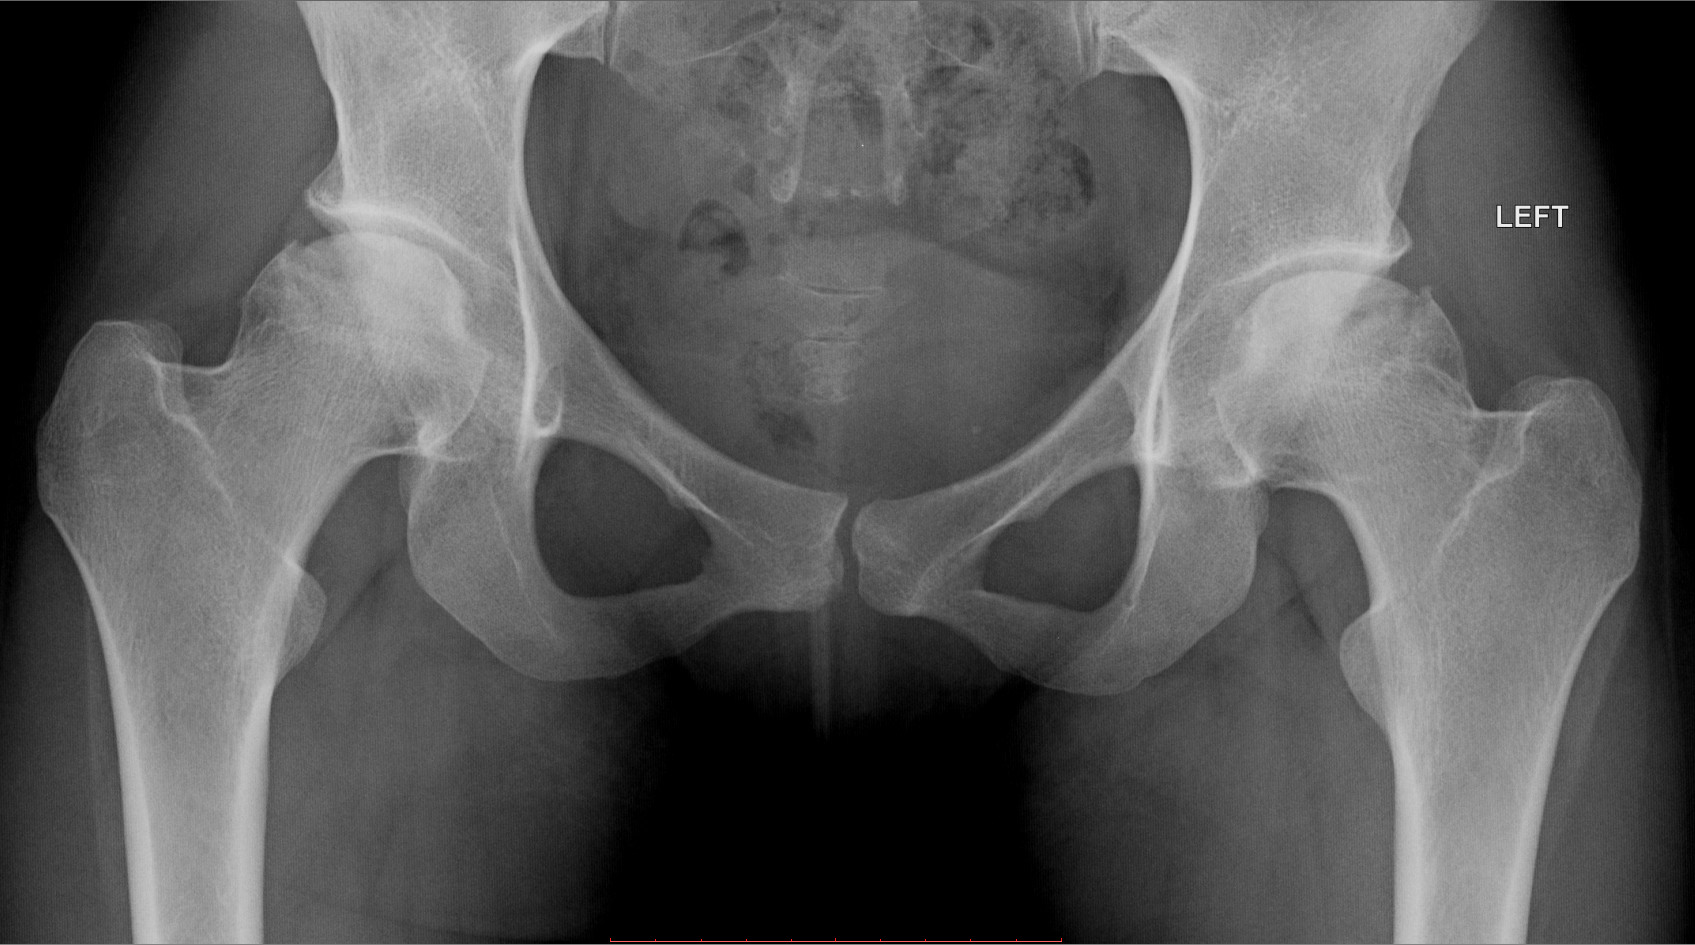

Оссификация тазобедренных суставов: что это и как проявляется?